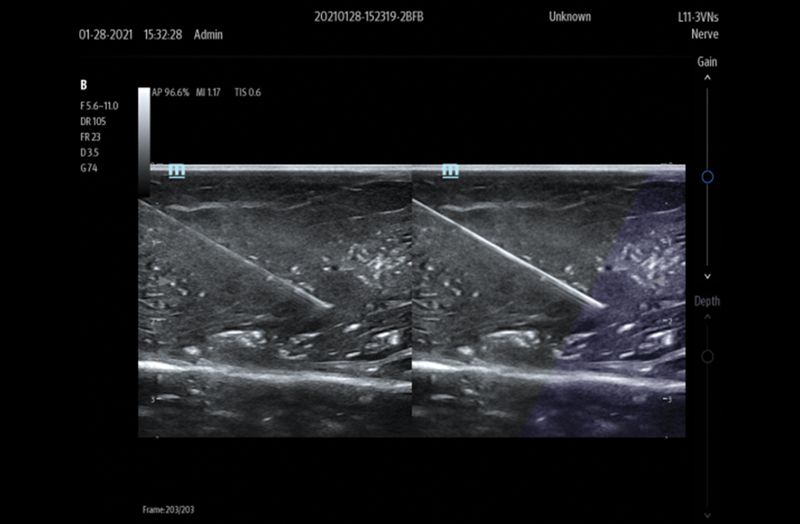

Ultrasound Reimagined

Advanced Technologies

Clinical Certainty Within Reach